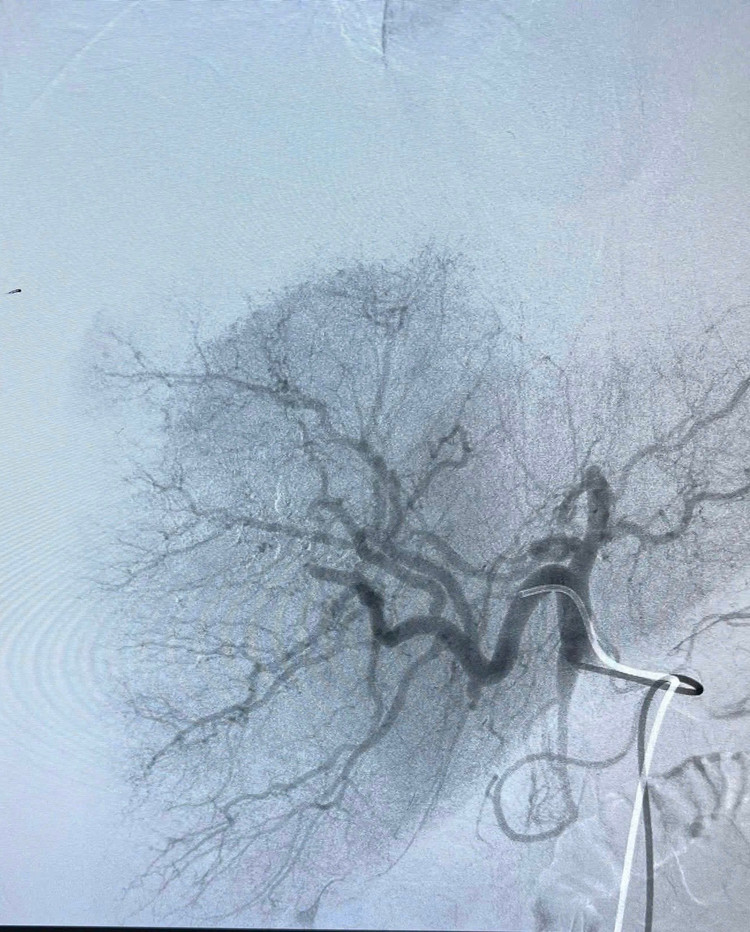

Nhận định đây là ca bệnh nguy kịch, kíp trực khoa Chẩn đoán hình ảnh đã nhanh chóng hội chẩn cùng các bác sĩ khoa Ngoại tiêu hóa khẩn trương xử trí cấp cứu, thực hiện can thiệp Nút mạch cầm máu, dẫn lưu ổ áp xe, chọc hút dịch và rửa ổ bụng dưới hướng dẫn của siêu âm.

Can thiệp Nút mạch cầm máu - Ảnh BVCC